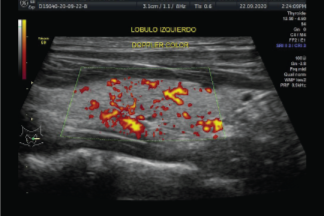

Una biopsia con aguja fina de un nódulo tiroideo es un procedimiento sencillo y seguro. Generalmente la biopsia se hace guiada por ultrasonido para asegurar la colocación precisa de la aguja en el nódulo tiroideo. El procedimiento es menos invasivo que la biopsia quirúrgica, deja poco o nada de cicatriz, y no involucra la exposición a la radiación ionizante.

Se insertará la aguja en el nódulo tiroideo a través de la piel. Luego de obtener la muestra, la cual toma algunos segundos, la aguja se retira.

Nuevas agujas son usadas para obtener nuevas muestras. Se obtendrán varias muestras de células, insertando la aguja en diferentes partes del nódulo, usualmente entre 2 a 6 veces.